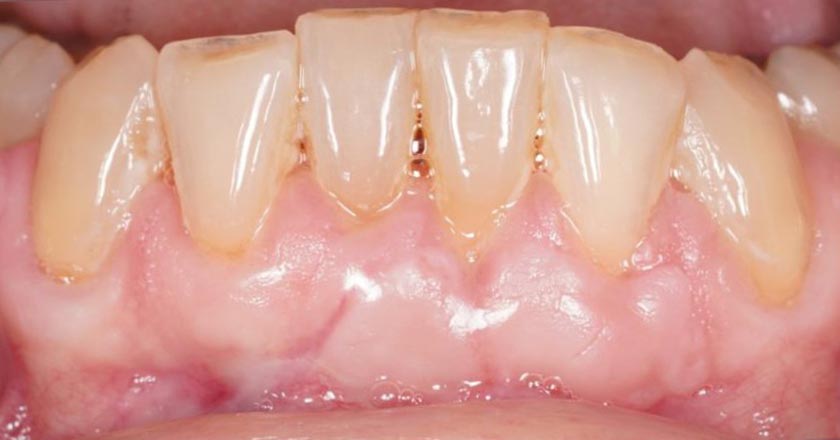

Gum Disease - Before And After

Gum disease scaling and root planing – before treatment

Gum disease scaling and root planing – after treatment